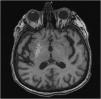

Hemiballism/hemichorea (HH) is a hyperkinetic movement disorder observed mostly in older adults with cerebrovascular diseases. Although the symptoms improve without any treatment, lesioning or DBS (deep brain stimulation) may be rarely required to provide symptomatic relief for patients with severe involuntary movements. HH is a rare complication of uncontrolled diabetes. There are only a few reported cases of diabetic HH that have been surgically treated. Thus, herein, we have reported the case of a 75-year-old female with type-II diabetes mellitus that presented with disabling involuntary limb movements of the left side, despite being treated conservatively for six months. DBS targeting the globus pallidus internus (GPi) and ventral intermediate (Vim) thalamic nucleus was performed. Complete resolution of symptoms was achieved with a combined stimulation of the thalamic Vim nucleus (at 1.7 mA) and GPi (at 2.4 mA). The combined stimulation of the Vim nucleus and GPi effectively resolved the diabetes-induced HH symptoms in our patient. Thus, although certain conclusions cannot be drawn due to the rarity of the surgically treated patients with HH, the combined stimulation is a novel treatment option for resistant HH.